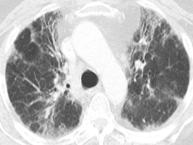

从这张图片上,我们看到两种密度,高密度的是磨玻璃影,而低密度可能是正常的肺组织,也可以是由于小气道疾病引起的。

这是另外一个例子,双肺有斑片状的磨玻璃影,同时看到了有少量囊腔,还看到了正常密度的肺脏,双下肺靠近胸膜的地方有少量实变。